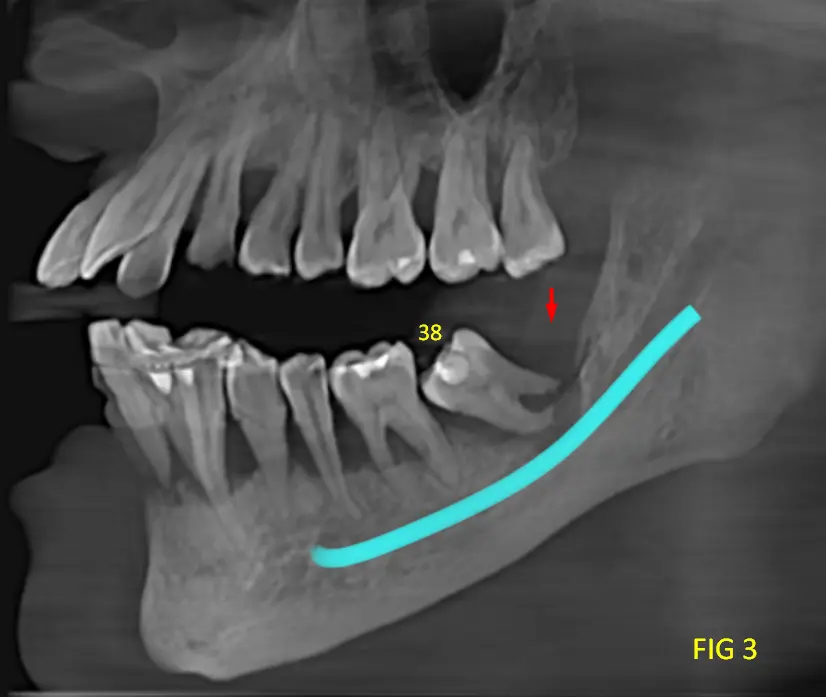

Se observa disminución marcada del soporte óseo alrededor de múltiples piezas, con exposición radicular extensa como el caso de las piezas dentarias 46 y 38, ver cortes tangenciales (ver Fig 2 y 3), lo que radiográficamente se correlaciona con movilidad dentaria clínica. En algunos sectores se aprecia compromiso óseo severo, con reducción importante de la altura del reborde alveolar.